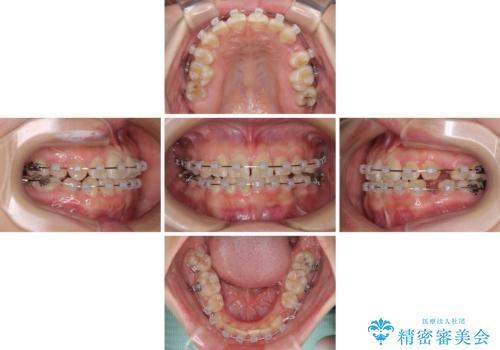

親知らずの抜歯により埋もれた奥歯周辺の歯肉が切除され、矯正装置が装着できるようになりました。

奥歯の移動、特に下顎大臼歯の移動は時間がかかることが多く、3年以上の治療期間を想定していましたが、想像以上に動きがよく、2年強で終えることができました。